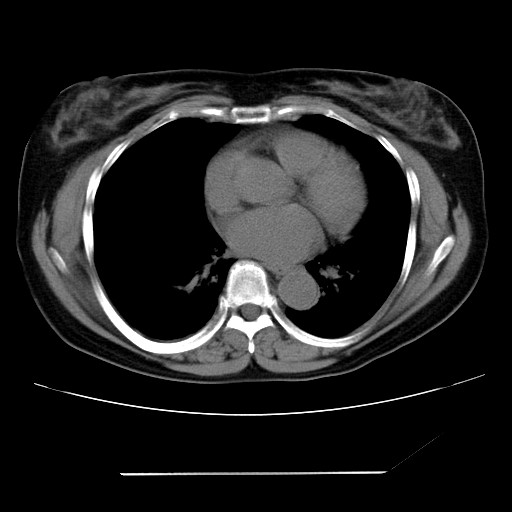

标题: CT24018:女性,62岁,咳嗽4年,无热,胸部CT扫 [打印本页]

女性,62岁,长期咳嗽,既往从事工作有粉尘接触,有高血压病史,110/150mmhg,近日咳嗽加重,脸面浮肿,请大家帮看下,

1、尘肺;2、慢性支气管炎合并肺部感染;3、心影增大(左房、左室大),考虑高血压性心脏病。

心包有积液吗?

慢支并肺部炎症;右肺结核球?主肺动脉、右肺动脉影不宽,右心室不大,不支持肺心病;无心包积液。

右肺无结核球,是肝上缘